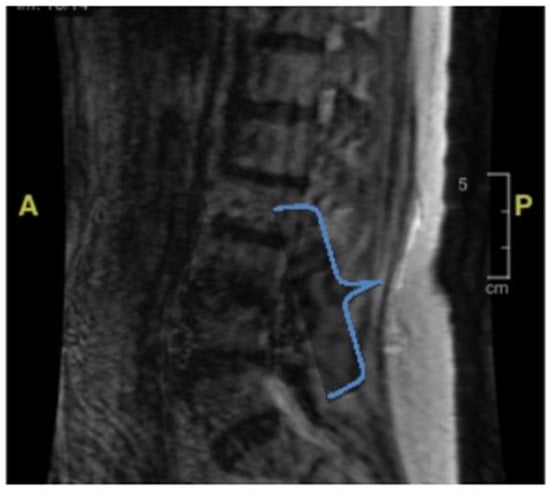

Her second hospital admission was precipitated by repeated ground-level falls from severe bilateral leg weakness. On this occasion, she described worsening back pain with ambulation. She also developed a left facial droop during the second admission. Extensive imaging, including another MRI and CT scan, showed no ischemic changes in the head and neck or acute stroke. Repeat cerebral MRI with and without contrast was negative (Figure 2). Lumbar spine MRI showed advanced degenerative disk disease but no significant pathology explaining her bilateral lower-extremity weakness (Figure 3). Lumbar spine CT showed moderate spinal stenosis at the two lowest vertebrae of the lumbar spine and a 2 mm anterolisthesis. The patient did not exhibit urinary or fecal incontinence.

During the third admission, she developed diarrhea with a one-week duration. Stool studies confirmed campylobacteriosis, which was treated with azithromycin. During this hospitalization, the patient once again developed a left-sided facial droop. Extensive imaging, including further head CT and CT angiography (CTA), showed no acute head and neck vascular ischemic changes. There were no spinal MRI findings (Figure 3) that could explain her lower-extremity weakness. During this admission, she underwent her first lumbar puncture, with the results displayed in Table 1. Ultimately, the patient was diagnosed with Bell’s palsy and completed 7 days of prednisone and 5 days of acyclovir. By this point, she had developed an immense fear of falling and was discharged to a rehabilitation facility for mobility and activities of daily living therapy.

Figure 3. Lumbar spine MRI without contrast. The bracket encloses the area where there appear to be degenerative changes, which are most pronounced at the lumbar vertebral levels of L3–L4 and L4–L5. There is also some degree of spinal canal stenosis, at least moderate at L3–L4. Based upon the MRI, there are no acute fractures or subluxation.